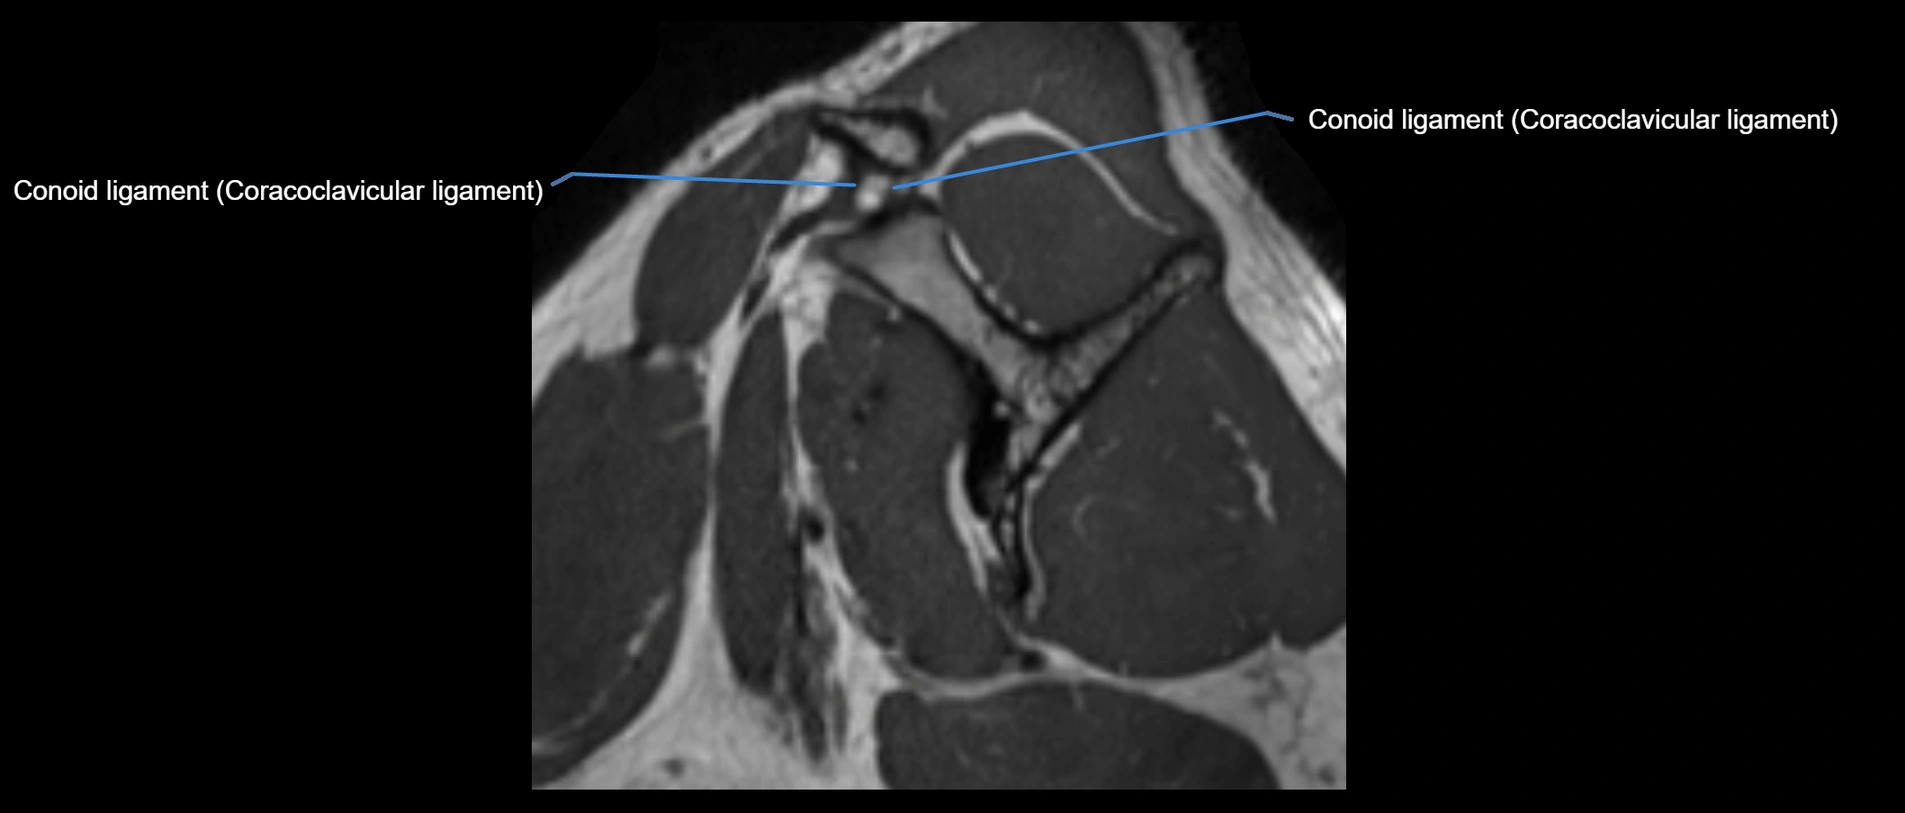

MRI images

image

• Synergy: Works with coracoclavicular ligaments (conoid and trapezoid) for vertical stability of shoulder girdle.

• Excellent for assessing joint capsule, coracoclavicular ligaments, and periarticular edema.